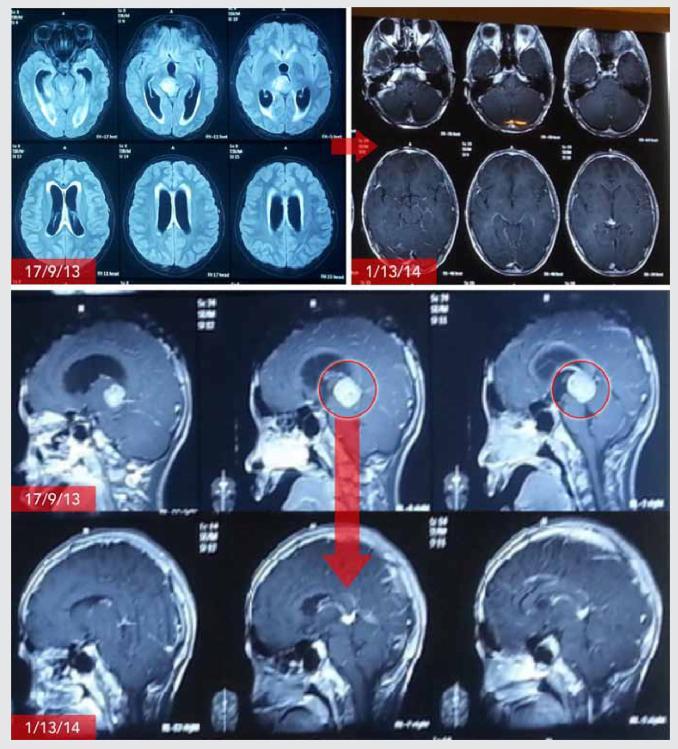

ECCT治疗的过程包含3个步骤:(1)通过MRI或CT定位肿瘤,(2)设计电容电极,计算肿瘤治疗区域内电场分布,(3)根据电场强度分布优化电极设计,使肿瘤细胞获得足够强度的电场,并考虑到与肿瘤位置相连的静脉通道来处理死亡细胞。

电场疗法治疗脑肿瘤的大致过程:计算电场,治疗前后行CT检查。